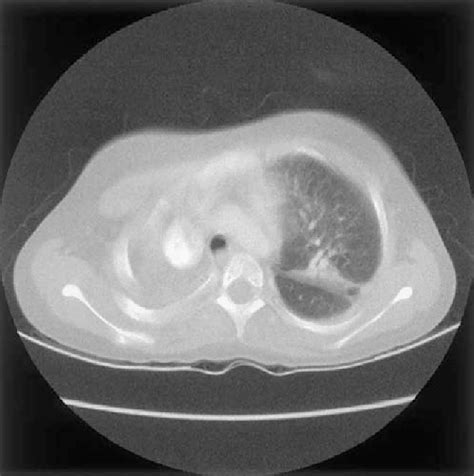

Diagnosing Nocardia Infections: The Detective Work

Alright guys, let’s talk about how doctors play detective to figure out if someone has a Nocardia infection . Because, as we’ve seen, the symptoms can be a bit vague and mimic other diseases, diagnosis isn’t always straightforward. The first and most crucial step is suspicion. If a patient presents with symptoms suggestive of infection, especially if they have risk factors like a weakened immune system or exposure to soil, doctors will start thinking about Nocardia. The gold standard for diagnosis is microbiological culture . Samples are taken from the suspected site of infection – this could be sputum from the lungs, pus from a skin abscess, cerebrospinal fluid from the brain, or even tissue biopsies. These samples are then sent to the laboratory where microbiologists try to grow the Nocardia bacteria. This isn’t always easy because Nocardia can be slow-growing, and they require specific culture media and incubation conditions. Sometimes, special techniques are needed to help the bacteria grow, like using modified techniques to isolate them from other bacteria present in the sample. Once Nocardia is successfully cultured, it can be identified using various laboratory methods, including Gram staining, acid-fast staining (remember those waxy walls?), and biochemical tests. Molecular methods, like PCR (polymerase chain reaction), are also increasingly being used for faster and more accurate identification. Imaging studies play a vital role too. Chest X-rays or CT scans can help visualize lung involvement, showing infiltrates, abscesses, or nodules. MRI or CT scans of the brain are essential for detecting brain abscesses. These imaging findings, combined with clinical presentation and laboratory results, help paint a clearer picture. It’s a multi-pronged approach, really. Sometimes, the diagnosis can be tricky, and it might take a few tries to get the right sample or the right culture conditions. Histopathology, the examination of tissue under a microscope, can also provide clues, showing characteristic inflammatory patterns and sometimes even the presence of the bacteria. Susceptibility testing is also a critical part of the diagnostic process. Once Nocardia is identified, the lab will test which antibiotics are most effective against it. This is super important because Nocardia can be resistant to certain drugs, and choosing the right antibiotic early on can make a huge difference in treatment success and preventing complications. So, it’s a combination of clinical suspicion, careful sample collection, specialized laboratory techniques, advanced imaging, and antibiotic susceptibility testing that allows us to finally unmask these elusive Nocardia infections. It’s a real team effort between the doctors, nurses, and lab scientists to get to the bottom of it.